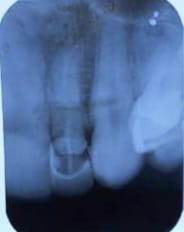

Em sua página oficial na rede social Twitter, o Flamengo publicou o raio x da boca do jogador, onde é possível ver a fratura dental.

A fratura dentária pode ser causada por diversas possibilidades, como o bruxismo, pela mordida de algum alimento muito resistente, pelo desequilíbrio oclusal ou mesmo por um trauma, como foi o caso do jogador de futebol Gabigol.

Quando um paciente passa pelo tratamento de canal, a probabilidade de haver uma fratura dental também aumenta, já que o processo cirúrgico pode ocasionar um desgaste na região, tornando-a mais frágil durante o procedimento odontológico.

Nos casos de diagnóstico de fratura dentária, o paciente têm duas possibilidades para o seu tratamento. Se o diagnóstico for de uma fratura coronária, o dente pode ser restaurado ou receber um implante.

Porém, se tratando de uma fratura radicular, que se demonstra como uma lesão mais complexa, o dente fraturado deve ser extraído e outro deve ser implantado. Nesse caso, o paciente também pode utilizar de uma prótese dentária.